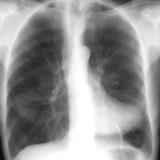

Case 2  Lung cancer and

Peric calcification

Date: 03/17/2004

Views: 2512